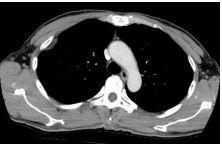

5. 57 y female, breast ca for survey